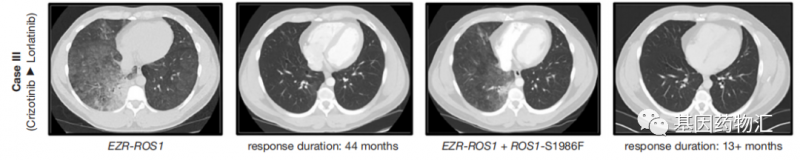

第三个病例当中的患者只有32岁,极少吸烟,确诊时为晚期非腺癌,肺部及腋窝都存在转移病灶。免疫组化提示患者存在ROS1重排,因此患者在一线治疗当中使用了克唑替尼,250 mg每天两次。

疗效非常持久,患者在44个月内持续保持着缓解。但在随后的随访当中,影像学检查显示患者肺右下叶的病灶再次开始生长,并有新的淋巴管扩散证据,确诊为复发。

重新进行活检,二代测序结果提示患者存在EZR-ROS1融合以及ROS1 -S1986F耐药突变,即对于克唑替尼已经耐药。医生选择了劳拉替尼二线治疗方案——劳拉替尼方案在ROS1适应症上并没有获批,属于超适应症用药。但从结果上来说,效果非常理想,自用药开始后的13个月随访时,患者仍保持着临床缓解,未见进展。